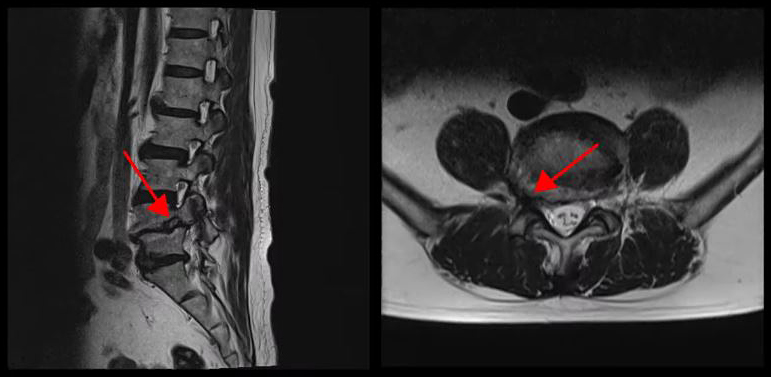

<4-5번 추간공협착증>

<4-5번 척추전방전위증>

<5-1번 디스크 파열>

이 환자분의 허리 MRI를 보면 4번, 5번 오른쪽에 심한 추간공협착증과 2단계의 척추전방전위증이 있는데, 특히 척추전방전위증 때문에 추간공이 많이 좁아져 있는 상태입니다. 또 왼쪽의 다른 마디에 디스크 파열이 있으나 환자분이 왼쪽으로는 증상이 전혀 없는 것으로 보아 이 디스크 파열은 통증을 일으키지 않는 무증상의 디스크 파열입니다.

이렇듯 4번, 5번 마디의 심한 추간공협착증과 척추전방전위증으로 인해 이 환자분은 다리에 마비가 왔고, 발목에 힘이 빠져 거의 걷지 못하는 상태였습니다. 새벽에 잠에서 깨 화장실을 갈 때는 네 발로 기어갈 정도로 증상이 심했습니다. 신경주사도 많이 맞아봤지만 통증이 전혀 줄지 않아서 결국 수술을 결심하셨는데요. 대학병원을 비롯해 정형외과 및 신경외과 등 아홉 군데 병원에서 진료를 받았지만, 어려운 수술이라고 말하면서 척추유합술, 감압술 등 병원마다 제시하는 수술방법이 다 달라 큰 혼란을 겪으셨습니다. 게다가 수술 후 후유증이나 잔존 증상에 대한 물음에 ‘있을 수도 있고 없을 수도 있다’라는 의사의 말에 수술을 고민하던 중 마지막이라는 생각으로 저희 모커리에 내원하셨습니다.